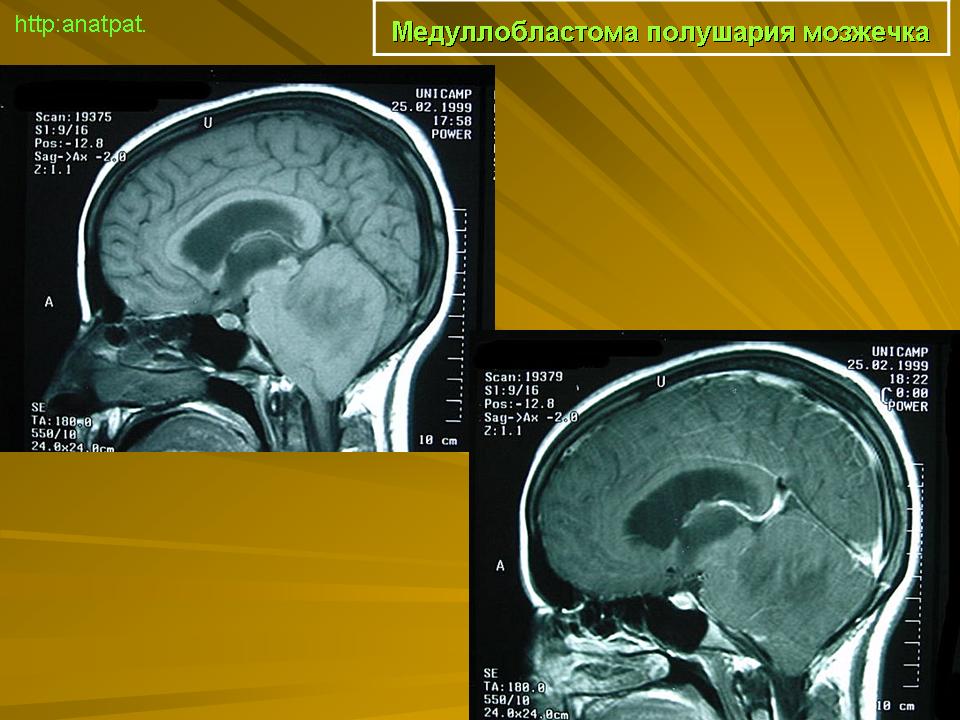

Медуллобластома - это опухоль, которая возникает из примитивных и эмбриональных клеток ЦНС. Локализируется исключительно в мозжечке и представляет 15-20% от детских опухолей мозга. 20% медуллобластом появляется в зрелом возрасте.

Это быстро растущая опухоль, очень злокачественна, имеющая тенденцию распространяться вдоль путей движения ликвора.

Вследствие локализации в мозжечке, обструкция путей циркуляции ликвора является достаточно частой и ранней, с последующей гидроцефалией. Синдром повышенного внутричерепного давления наряду с расстройствами равновесия, являются наиболее частыми и ранними признаками и симптомами.